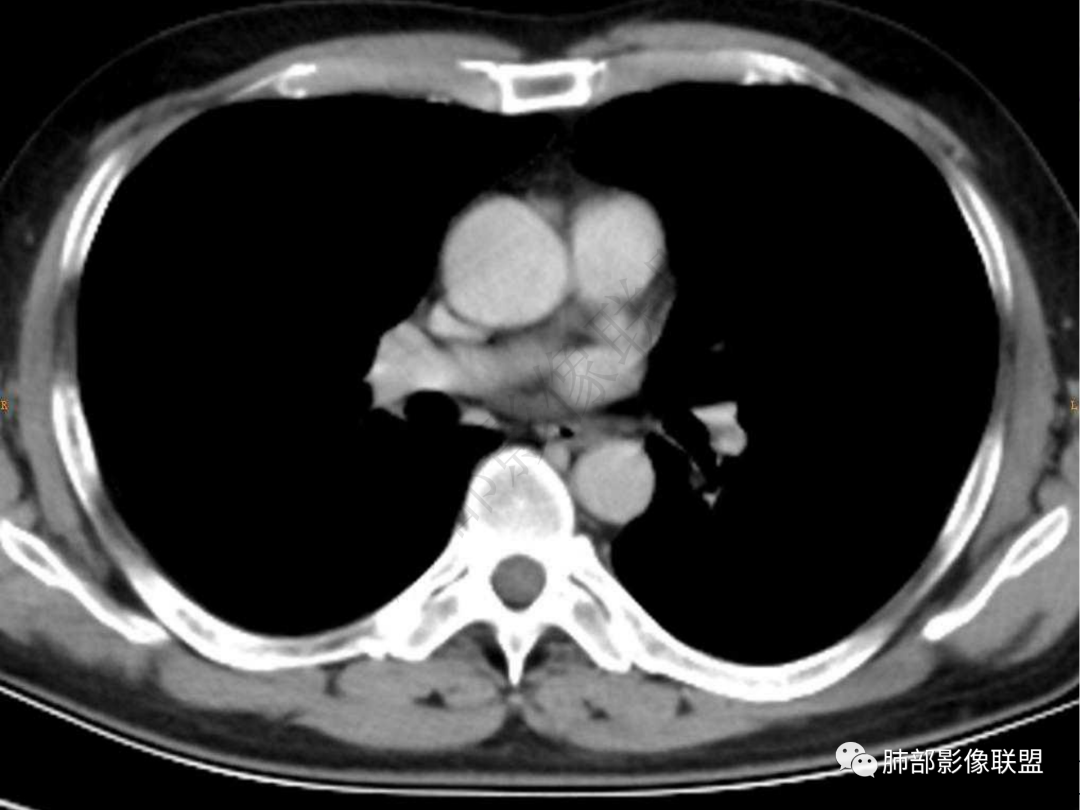

4.实性部分不均匀环形强化并显示一小范围低密度坏死区或空洞。较之肺窗,整体纵隔窗范围较小,提示病灶并不十分密实。抑或为不同时段图像。

5.双肺门及纵隔未见增大淋巴结。未见胸腔积液。

肺脓肿:可宽基底与胸膜相连,附近胸膜增厚——炎性特点

肺脓肿:边界模糊不清,或者块影为类圆形,无明显分叶,边缘平直为主,刀切征——炎性特点三、病灶周围特点:肺脓肿:病灶非远端有片状GGO——炎性特点四、近端支气管阻塞:肺脓肿:常有引流支气管伴管壁增厚或者支气管沿洞壁走行。五:坏死壁:肺脓肿:大多壁厚,少数壁薄,没有壁结节,内壁清楚光整——炎性特点

肺脓肿:环形强化,强化较显著。如出现明显囊壁样强化甚至边缘“憩室”样突出,高度支持肺脓肿。